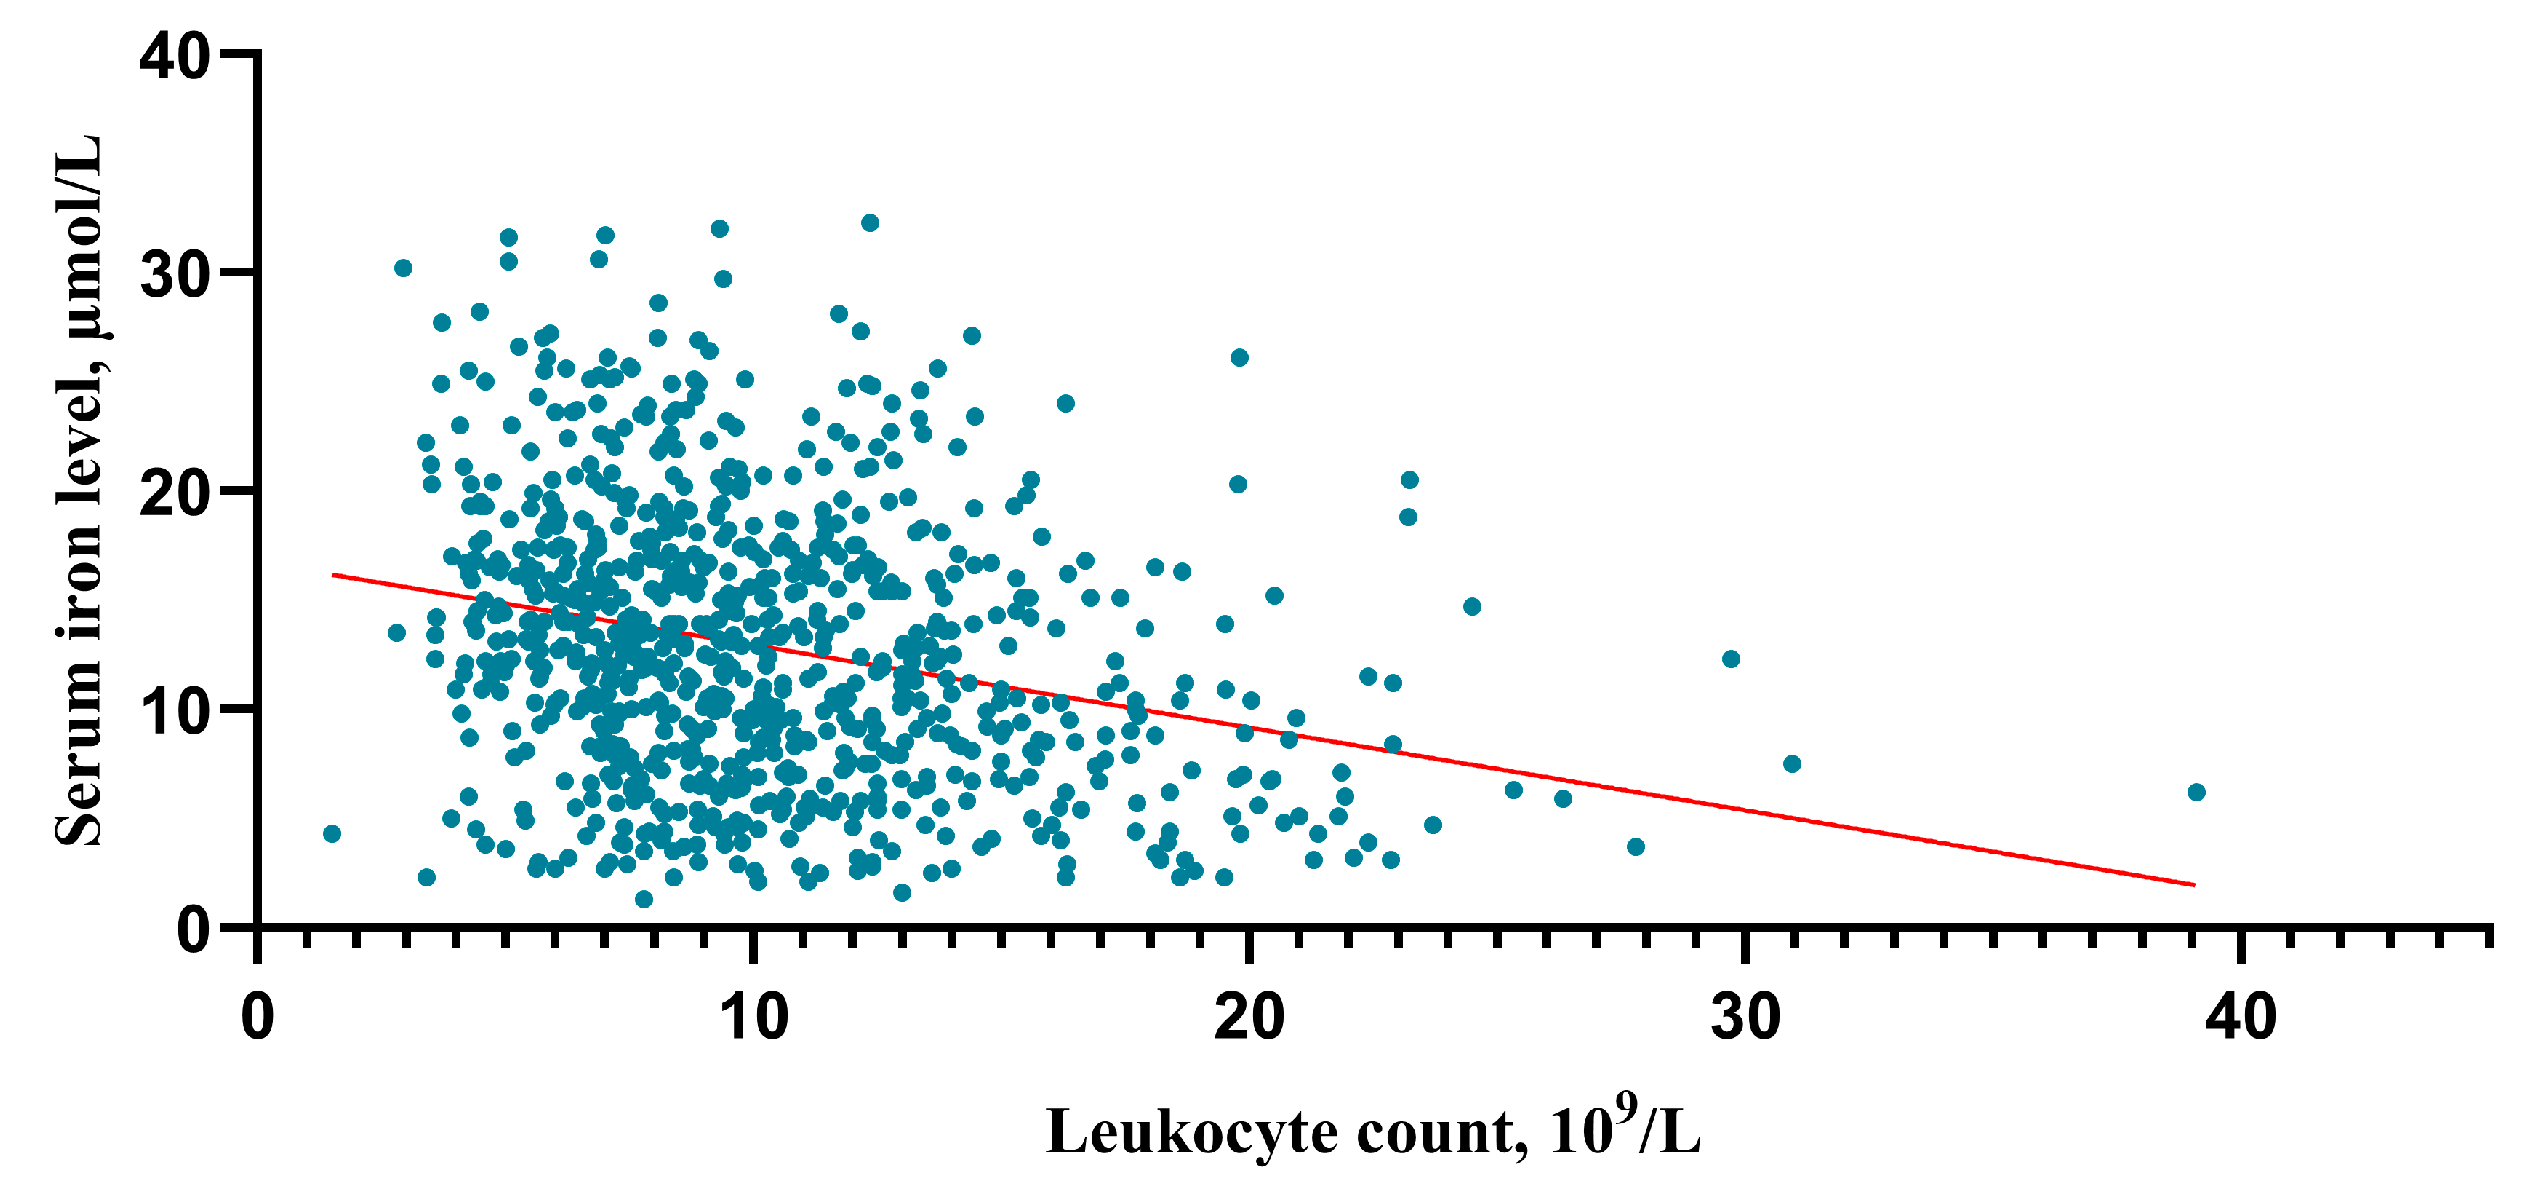

4.3. Association of Serum Iron with HHgrade and mFisher Grade

4.4. Association of Serum Iron with Poor 3-Month Functional Outcome